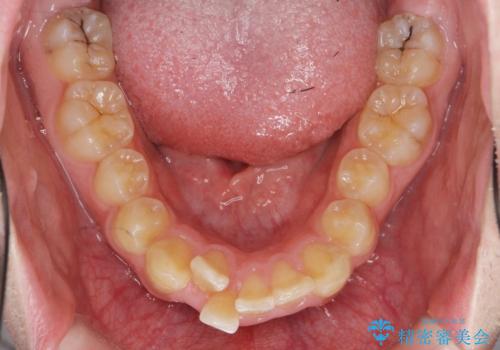

ガタつきの大きい前歯 インビザラインによるマウスピース矯正治療

- ガタつきの目立つ前歯の改善を求めて来院されました。

上顎前突、がたつきを改善すべく上顎臼歯の後方移動・ディスキングを行い歯並びの改善を計画します。

食事・歯ブラシ時以外の時間にしっかりとマウスピースを装着していただけたのでガタつきは大きく改善し良好な歯並びを得ることができました。